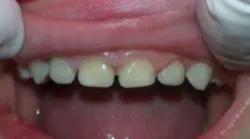

A strip crown technique (in this case, Activa BioActive-Restorative) requires fewer steps, takes less time, offers a better seal against secondary caries, and provides a more durable and fracture-resistant restoration. First, I trim and prefit Nowak strip crowns so they are even with the sulcus (figure 2). Because the prep in these cases is usually quite minimal, I typically do not need local anesthetic.